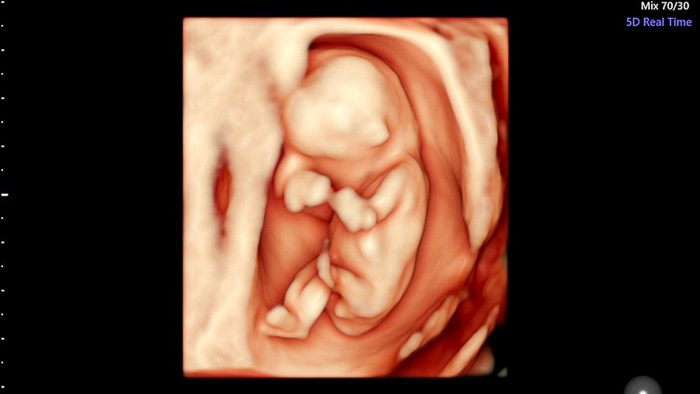

Thai 5 tháng tương đương với 20 tuần, lúc này thai đã lớn và có đầy đủ tất cả các bộ phận. Việc phá thai 5 tháng tuổi ít nhiều cũng sẽ gây ảnh hưởng xấu đến sức khỏe của thai phụ nếu như phá thai 5 tháng không đúng cách sẽ khiến thai phụ gặp nhiều biến chứng nguy hiểm, thậm chí còn đe dọa đến tính mạng.